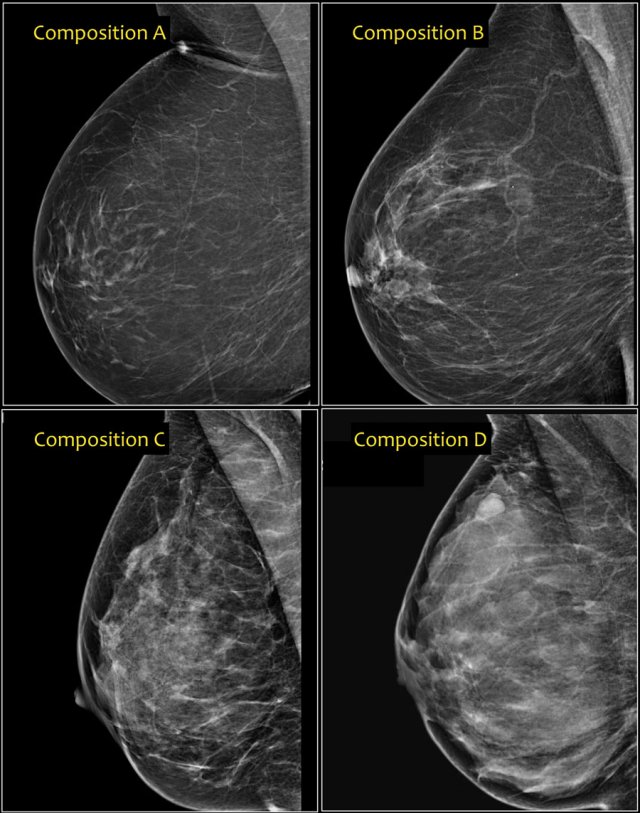

In the BI-RADS edition 2013 the assignment of the breast composition is changed into a, b, c and d-categories followed by a description:

• a- The breast are almost entirely fatty.

Mammography is highly sensitive in this setting.

• b- There are scattered areas of fibroglandular density.

The term density describes the degree of x-ray attenuation of breast tissue but not discrete mammographic findings.

• c- The breasts are heterogeneously dense, which may obscure small masses.

Some areas in the breasts are sufficiently dense to obscure small masses.

• d - The breasts are extremely dense, which lowers the sensitivity of mammography.

Notice in the left example the composition is c - heterogeneously dense, although the volume of fibroglandular tissue is less than 50%.

The fibroglandular tissue in the upper part is sufficiently dense to obscure small masses.

So it is called c, because small masses can be obscured.

Historically this would have been called an ACR 2: 25-50% density.

The example on the right has more than 50% glandular tissue and is also called composition c.